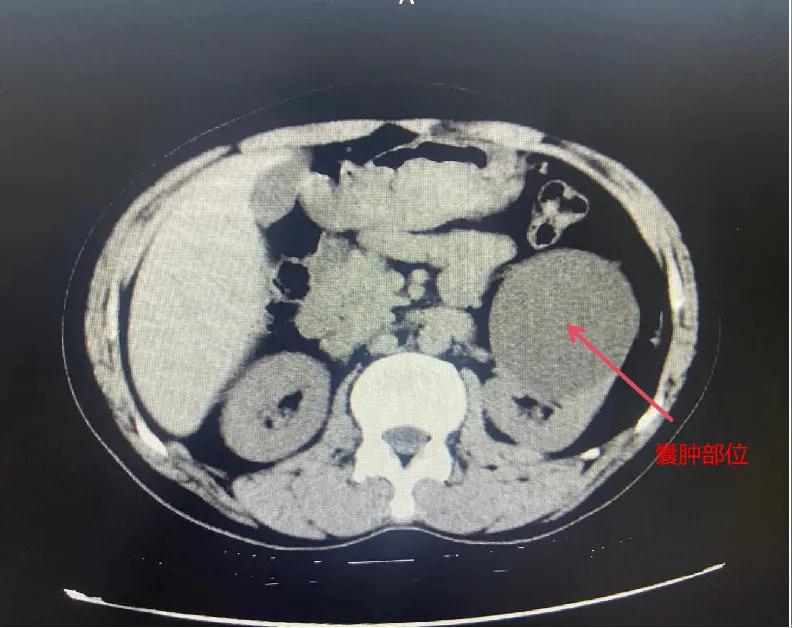

漯河市骨科醫(yī)院泌尿外科開展后腹腔鏡下腎囊腫去頂減壓術

近日,漯河市骨科醫(yī)院(漯河醫(yī)專二附院、漯河市立醫(yī)院)連續(xù)收治2例腎囊腫患者。泌尿外科主任閆衛(wèi)甫和副主任醫(yī)師王金柱等醫(yī)師團隊經討論研究后,決定為患者采取后腹腔鏡下腎囊腫去頂減壓術,經過手術室、麻醉科等科室大力配合成功完成手術。

閆衛(wèi)甫表示,后腹腔鏡技術是一種微創(chuàng)外科手術方法,它通過在后腹腔(即腹膜后的空間)建立一個手術空間,利用腹腔鏡器械進行手術操作。這種技術特別適用于泌尿系統(tǒng)等后腹腔臟器的手術。與傳統(tǒng)手術相比具有創(chuàng)傷小、恢復快、并發(fā)癥少、視野清晰等優(yōu)點。與前腹腔鏡相比則具有對腹腔臟器干擾較少的優(yōu)點。目前,后腹腔鏡手術主要用于腎囊腫去頂減壓術、腎上腺腫瘤切除、早期腎癌根治術、腎腫瘤剜除術等。

腎囊腫是一種常見的腎臟良性疾病,其發(fā)病率逐年增加。近年來隨著腹腔鏡技術的迅速發(fā)展,后腹腔鏡下腎囊腫去頂減壓術成為治療腎囊腫的主要方法。該手術具有創(chuàng)傷小,手術時間短,術中出血少,術后康復快,出院時間短等優(yōu)點,并且術后復發(fā)率低,被認為是治療腎囊腫的理想術式。(盧 闖 聶方方 劉 旭 袁錦鈺)